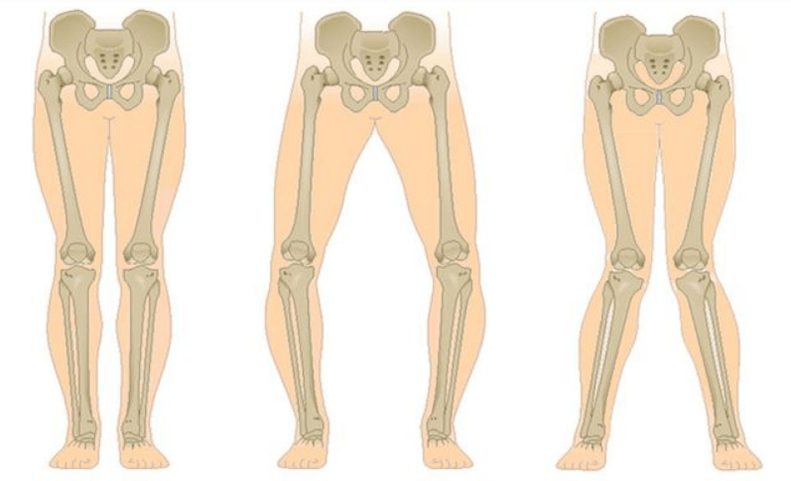

The last stage of gonarthrosis is distinguished by the fact that the pain becomes almost constant, causing anxiety not only while walking, but also at rest, and even at night, when patients have to look for a comfortable position to sleep.Movement is more limited: it is difficult to bend and straighten the leg completely.The joint becomes deformed and increases in volume.Valgus (X-shaped) or varus (O-shaped) deformity of the legs is often observed.The gait becomes unstable and waddles.In severe cases, a cane or crutches are needed.

With arthrosis (osteoarthrosis), in addition to the progressive destruction of cartilage, loss of its elasticity and shock-absorbing properties, bones are gradually involved in the process.Under load, sharp edges (exostoses) appear, which are mistakenly considered “salt deposits” - with classic arthrosis, no salt deposition occurs.As arthrosis progresses, it continues to “eat” the cartilage.Then the bone becomes deformed, cysts form there, all structures of the joint are affected, and the leg becomes bent.

Gonarthrosis affects the entire musculoskeletal system, disrupting the biomechanics of the spinal column and other large joints of the lower extremities.This can lead to herniated discs and arthritis of other joints.The second knee joint is overloaded (if the disease is one-sided), since the patient spares the sore leg, transferring the weight to the other, healthy one.